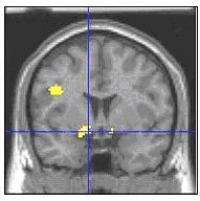

Brain scans showed that the left amygdala, a fear hub, and related structures, activated more in youth with the disorder than in healthy youth when asked to rate the hostility of an emotionally neutral face, as opposed to a non-emotional feature, such as nose width. The more patients misinterpreted the faces as hostile, the more their amygdala flared. Such a face-processing deficit could help account for the poor social skills, aggression, and irritability that characterizes the disorder in children, suggest Drs. Ellen Leibenluft, Brendan Rich, Daniel Pine, NIMH Mood and Anxiety Disorders Program, and colleagues, who report on their findings May 29, 2006 in the Proceedings of the National Academy of Sciences.

| The left amygdala and related structures (yellow area where lines intersect) are part of an emotion-regulating brain circuit where children with bipolar disorder showed greater activation than controls when rating their fear of neutral faces. Structural MRI image with functional MRI data superimposed. Credit: Source: NIMH Mood and Anxiety Disorders Program |

Using functional MRI, the researchers measured brain activity in 22 bipolar youth and 21 healthy subjects while they rated faces. In addition to the amygdala, other parts of the emotion-regulating circuit � nucleus accumbens, putamen, and left prefrontal cortex � were also hyperactive in patients, compared to healthy peers, during the emotional tasks. Patients rated themselves as more afraid, and they rated the faces as more hostile, compared to healthy peers. The groups did not differ on nose width ratings, confirming that the differences were specific to perceiving emotional processes.